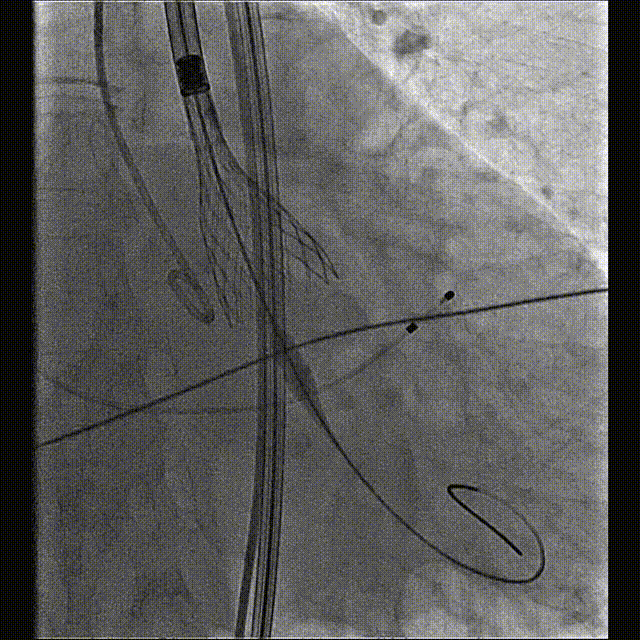

初始定位及释放

释放中评估